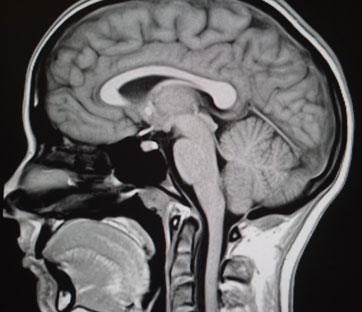

Quando si parla di protesi solitamente si pensa a un dispositivo artificiale che sostituisce un braccio, una gamba, del tessuto. Parti del corpo umano dunque, di cui si cerca talvolta di recuperare anche le funzionalità. Ora l’idea è ancor più ambiziosa: creare neuroprotesi intelligenti in grado di ripristinare l’attività delle reti neuronali, che potrebbero essere impiegate in caso di lesioni o malattie cerebrali, tra cui il morbo di Parkinson per fare solo un esempio. Al progetto, detto Ramp (Real neurons-nanoelectronics Architecture with MemristivePlasticity), sta lavorando un consorzio di ricerca europeo composto dal Neurochip Lab di Stefano Vassanelli, del dipartimento di Scienze biomediche dell’università di Padova che coordina le indagini, dall’università di Southampton, dall’università di Zurigo e dal laboratorio per la microelettronica e microsistemi del Consiglio nazionale delle ricerche.

In pratica gli scienziati hanno creato dei microchip, piccole piastrine in silicio, su cui sono stati integrati moltissimi sensori capaci di registrare l’attività elettrica di un’intera popolazione di neuroni ad alta risoluzione. E sono stati inseriti degli stimolatori in grado di evocare nella rete neuronale le stesse risposte che vengono indotte da input naturali esterni, come sensazioni tattili o visive. Le dimensioni dello strumento sono all’incirca quelle di un ago da siringa e la sperimentazione della tecnica, condotta per ora sui topi, ha dato esiti positivi.

“L’obiettivo – spiega Vassanelli che si dedica a questo filone di ricerca ormai da 15 anni, dopo il suo soggiorno al Max Planck Institutes of Biochemistry – è di preparare la strada per avere un giorno, tra 15-20 anni, delle neuroprotesi capaci di sopperire ad eventuali perdite o disfunzioni delle reti neuronali naturali”. Che si tratti di traumi, patologie neurodegenerative o altri tipi di malattie neurologiche, questo tipo di approccio potrebbe permettere il ripristino delle funzionalità del tessuto cerebrale.

Se si guarda più a breve termine invece, già nel giro di qualche anno le nuove tecnologie potrebbero permettere di migliorare la tecnica di stimolazione cerebrale profonda, utilizzata soprattutto nel trattamento dei casi più gravi del morbo di Parkinson, quando le altre terapie non sortiscono effetto. Si tratta di un procedimento condotto attraverso l’impianto in alcune zone del cervello di microelettrodi che producono impulsi elettrici. “Attualmente – spiega Vassanelli – gli elettrodi che vengono utilizzati hanno le dimensioni di due millimetri, noi invece utilizziamo siti di registrazione e stimolazione mille volte più piccoli di questi e ciò permetterà di evitare alcuni degli effetti indesiderati che purtroppo la stimolazione cerebrale profonda a volte porta con sé”. Se nel trattamento del morbo di Parkinson la procedura è ormai consolidata, attualmente si sta cercando di estenderne l’impiego anche in altre situazioni, come in caso di epilessia, di Alzheimer e, come ipotizza qualcuno, per facilitare il risveglio dal coma. È evidente che avere a disposizione nuove tecnologie, come quelle realizzate nell’ambito del progetto CyberRat e ora in fase di ulteriore sviluppo con Ramp, potrebbe senza dubbio aprire prospettive interessanti.